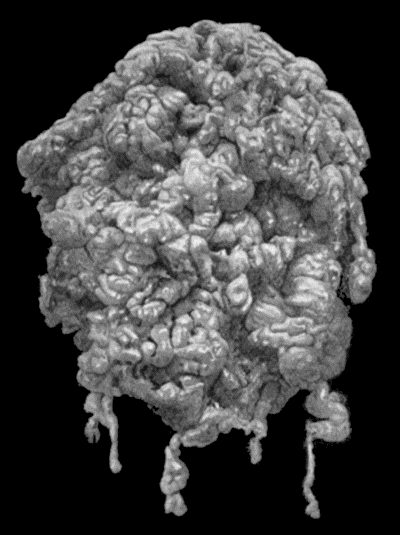

118.Shaft of the Femur after Acute Osteomyelitis 444

119.Femur and Tibia showing results of Acute Osteomyelitis 445